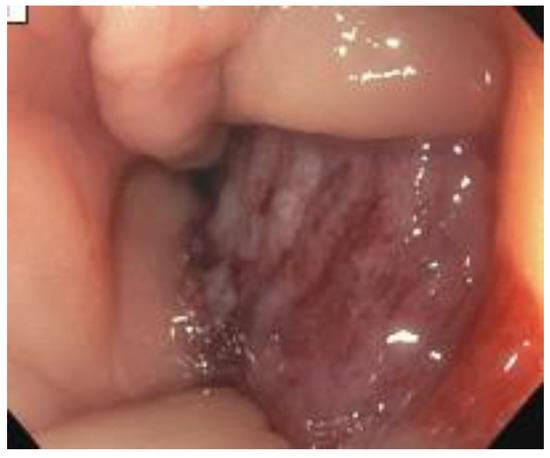

2. Case Presentation